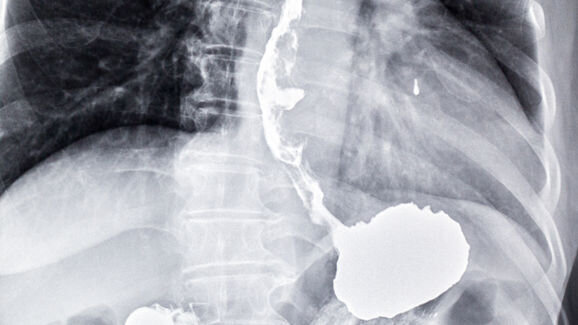

Doctors diagnose oesophageal and gastric cancers through endoscopies. However, the procedure is invasive and costs the NHS around £400–600 (approx. €560–850) per endoscopy. Only 2 per cent of patients who are referred for an endoscopy are diagnosed with oesophageal or gastric cancer.